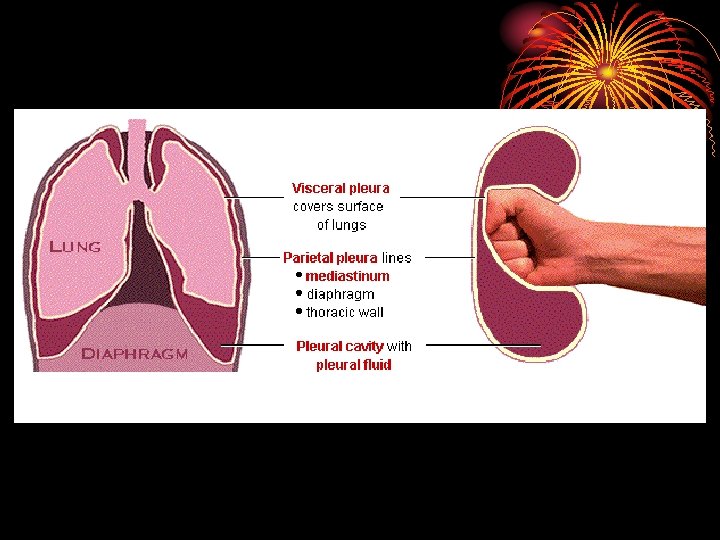

• area from 2. 5 cm 2 (trachea) to 11800 cm 2 in alveoli ? Air velocity. • 300 million alveoli, 70 m 2. • Alveoli lined by type 1 cells ( flat lining ) and type 11 cells ( granular pneumocytes secrete surfuctant ). • Pleura. • Respiratory muscles.